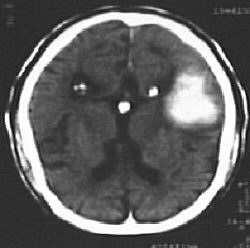

This is the fundal appearance of a child with

mental retardation. Refer to this picture

for question 4 & 5.